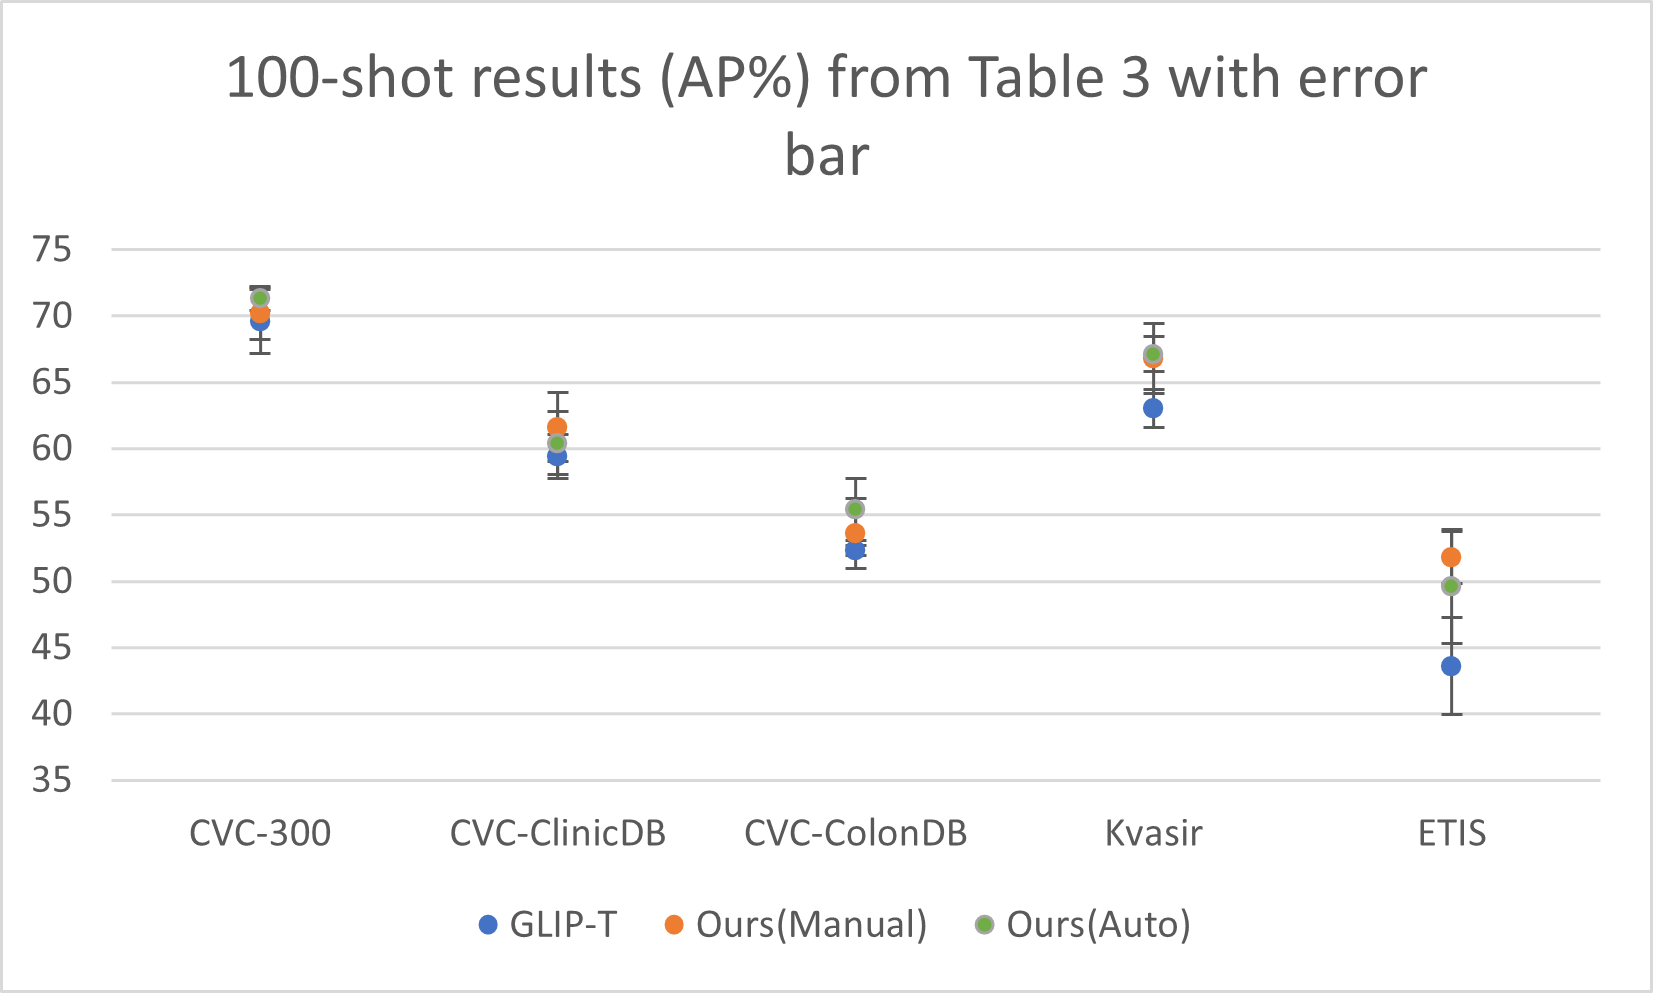

Transfer performance surpassing supervised methods To prove that text prompts are effective for cross-domain transfer, we conduct extensive experiments under both zero-shot domain transfer and supervised transfer (fine-tuning) settings. We include a series of supervised baselines: FasterRCNN, RetinaNet, and DyHead-L for comparisons. As illustrated in Figure 2, our full data fine-tuned models with well-designed medical prompts (dark blue) surpass the supervised baseline (e.g., DyHead-L in the figure) by a large margin across all datasets. Moreover, even zero-shot (brown) or 100-shot (sky blue) results on some datasets, e.g., CVC-300 and Luna-16, can rival the full data fine-tuned supervised models. The quantitative numbers are respectively shown in Table 2 for non-radiology datasets, Table 3 for polyp datasets, and Table 5 for radiology datasets. This is also supported by Figure 3 (right) where the VLMs significantly outperform the classical detection models with fully supervised learning, especially in few-shot settings.

Superior zero-shot transfer performance compared to the baseline Here, we provide strong evidence to show our approaches can empower the pre-trained VLM with remarkable zero-shot capability in the medical domain. As shown in Table 2 and Table 3, the prompts generated by our approaches tremendously improve the zero-shot performance of the GLIP models compared to the default ones. For example, on the polyp benchmarks, the out-of-box GLIP-T model only achieves an average AP of 4.1%, while the same model with our manually designed prompts reaches 41.3%. And this massive gain is not an exception. In addition, the models with well-designed prompts can reach an overall performance on par with the 100-shot fine-tuned baseline models on the polyp benchmarks (Table 3), and sometimes even rival the supervised baseline models trained with full-size data, e.g., on the CVC-300 dataset (69.9% AP for zero-shot v.s. 59.4% for Faster RCNN).

In this section, we demonstrate the standard deviation numbers and error-bar for our fine-tuning results. We use 3 different random seeds for our few-shot learning experiments to test whether our fine-tuning results are consistent across different random settings. The relative small standard deviation indicates that our method is not sensitive to the randomness.

| Method | CVC-300 | CVC-ClinicDB | CVC-ColonDB | Kvasir | ETIS | Avg. | |

| 100-Shot | GLIP-T | 57.6 | |||||

| Ours (Manual) | 60.8 | ||||||

| Ours (Auto) | 60.8 |